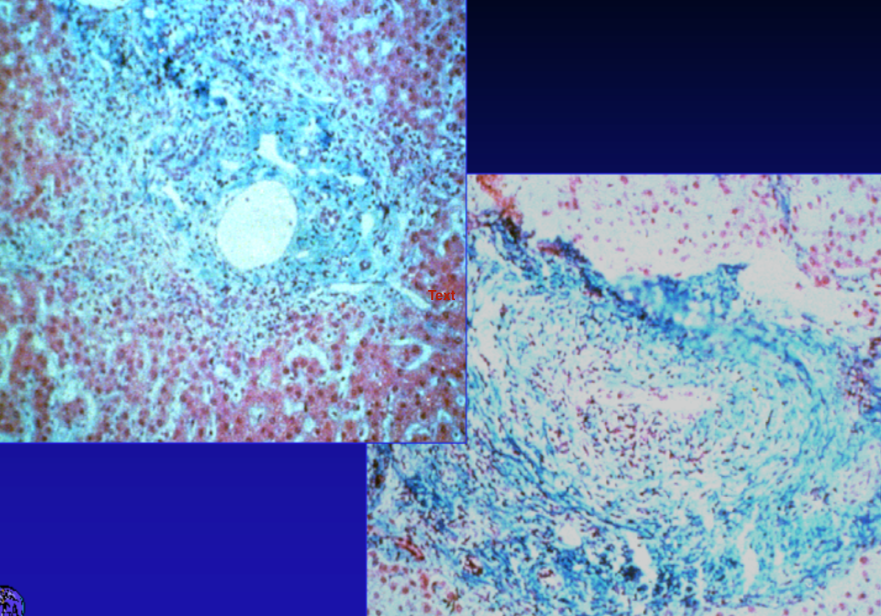

non-caseating granuloma in Crohn’s

crypt abcesses in ACUTE (INFECTIOUS) COLITIS

*architecture intact (unlike UC)

Cryptitis

crypt abscess